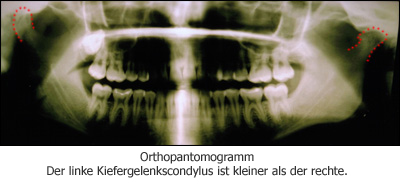

Radiologische Auswertung

Extreme condyläre Asymmetrie infolge wahrscheinlich zurückliegender Condylusfraktur TMJ(L) oder frühkindlichem Trauma. Zur Veranschaulichung sind die Konturen der Condylen auf der nachfolgenden Röntgenaufnahme rot nachgezeichnet.